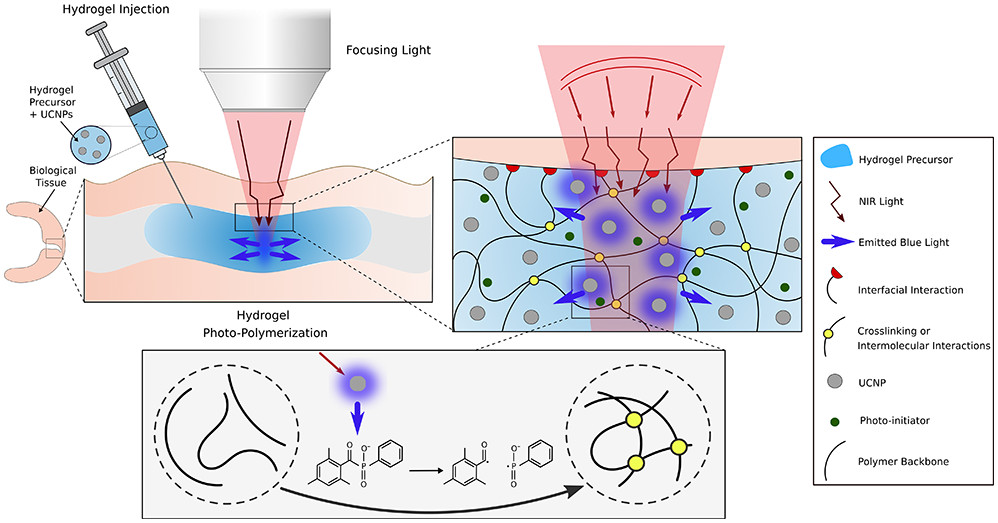

Karami P., Rana V. K., Zhang Q., Boniface A., Guo Y., Moser C., Pioletti D., NIR Light-Mediated Photocuring of Adhesive Hydrogels for Noninvasive Tissue Repair via Upconversion Optogenesis, Biomacromolecules, 23, 12, 5007–5017 (2022). |